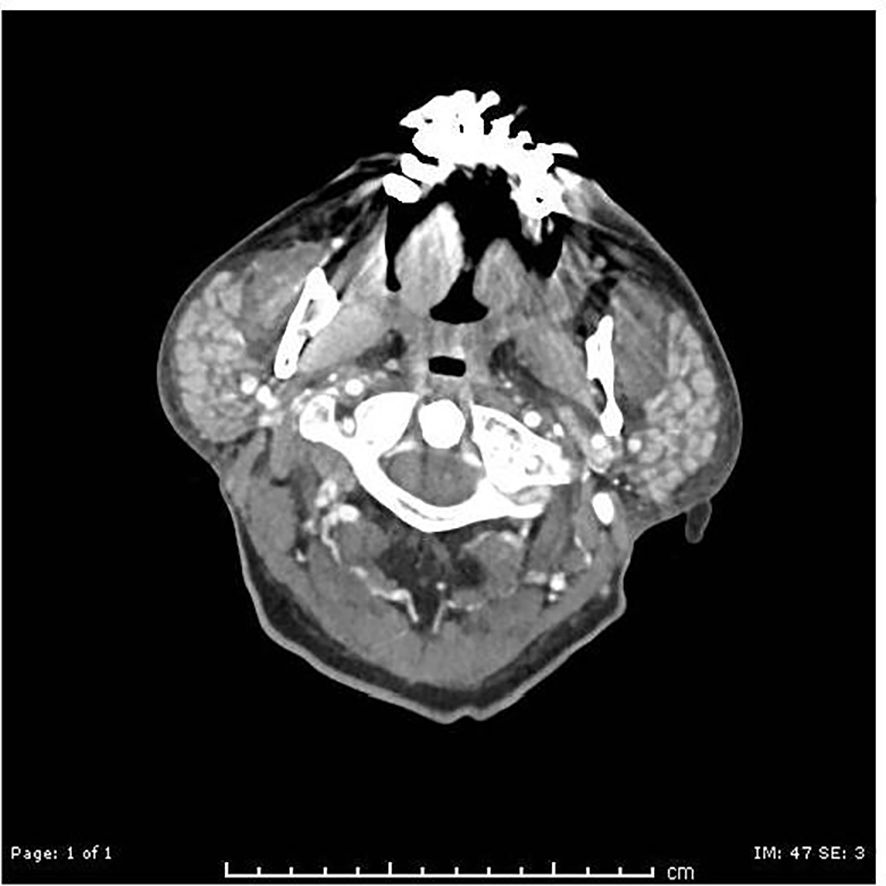

An MRI on day +23 showed worsening edema (Figures 2a–e). Plasmapheresis (PLEX) was performed for this patient for 5 total sessions given the MRI findings and a Foley catheter was placed for urinary retention.

Figure 2. (a, b) MRI cervical spine day +23: Sagittal T2-weighted image of the cervical spine showing T2 hyperintense lesions in the spinal cord extending from craniocervical junction to upper cervical spinal cord suggestive of demyelinating lesions. (c) MRI cervical spine day +23: Axial T2-weighted image of the cervical spine at the level of C2 showing T2 hyperintense lesion in right lateral aspect/periphery of the cord which can be seen with demyelinating disease. (d, e) MRI thoracic spine day +23: Sagittal T2-weighted STIR image showing scattered hyperintense lesions in the spinal cord, with some of these lesions (2nd image, post contrast T1+C) showing enhancement.